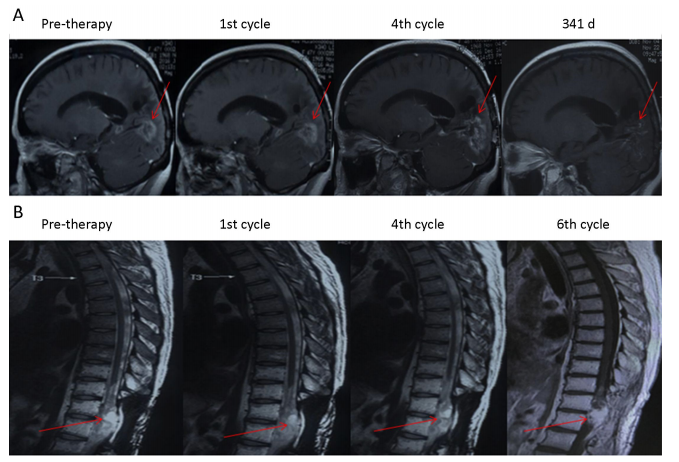

1研究發(fā)現(xiàn),綠原酸治療對(duì)部分患者(P3P4)有效,使腫瘤病灶縮小,達(dá)到穩(wěn)定疾病狀態(tài)(SD)。P3P4的無(wú)進(jìn)展生存期(PFS)分別為8.1個(gè)月和4.9個(gè)月,總生存期(OS)均超過(guò)16.5個(gè)月,且至今仍存活。

P3和P4患者綠原酸治療前后的磁共振成像(MRI)圖像